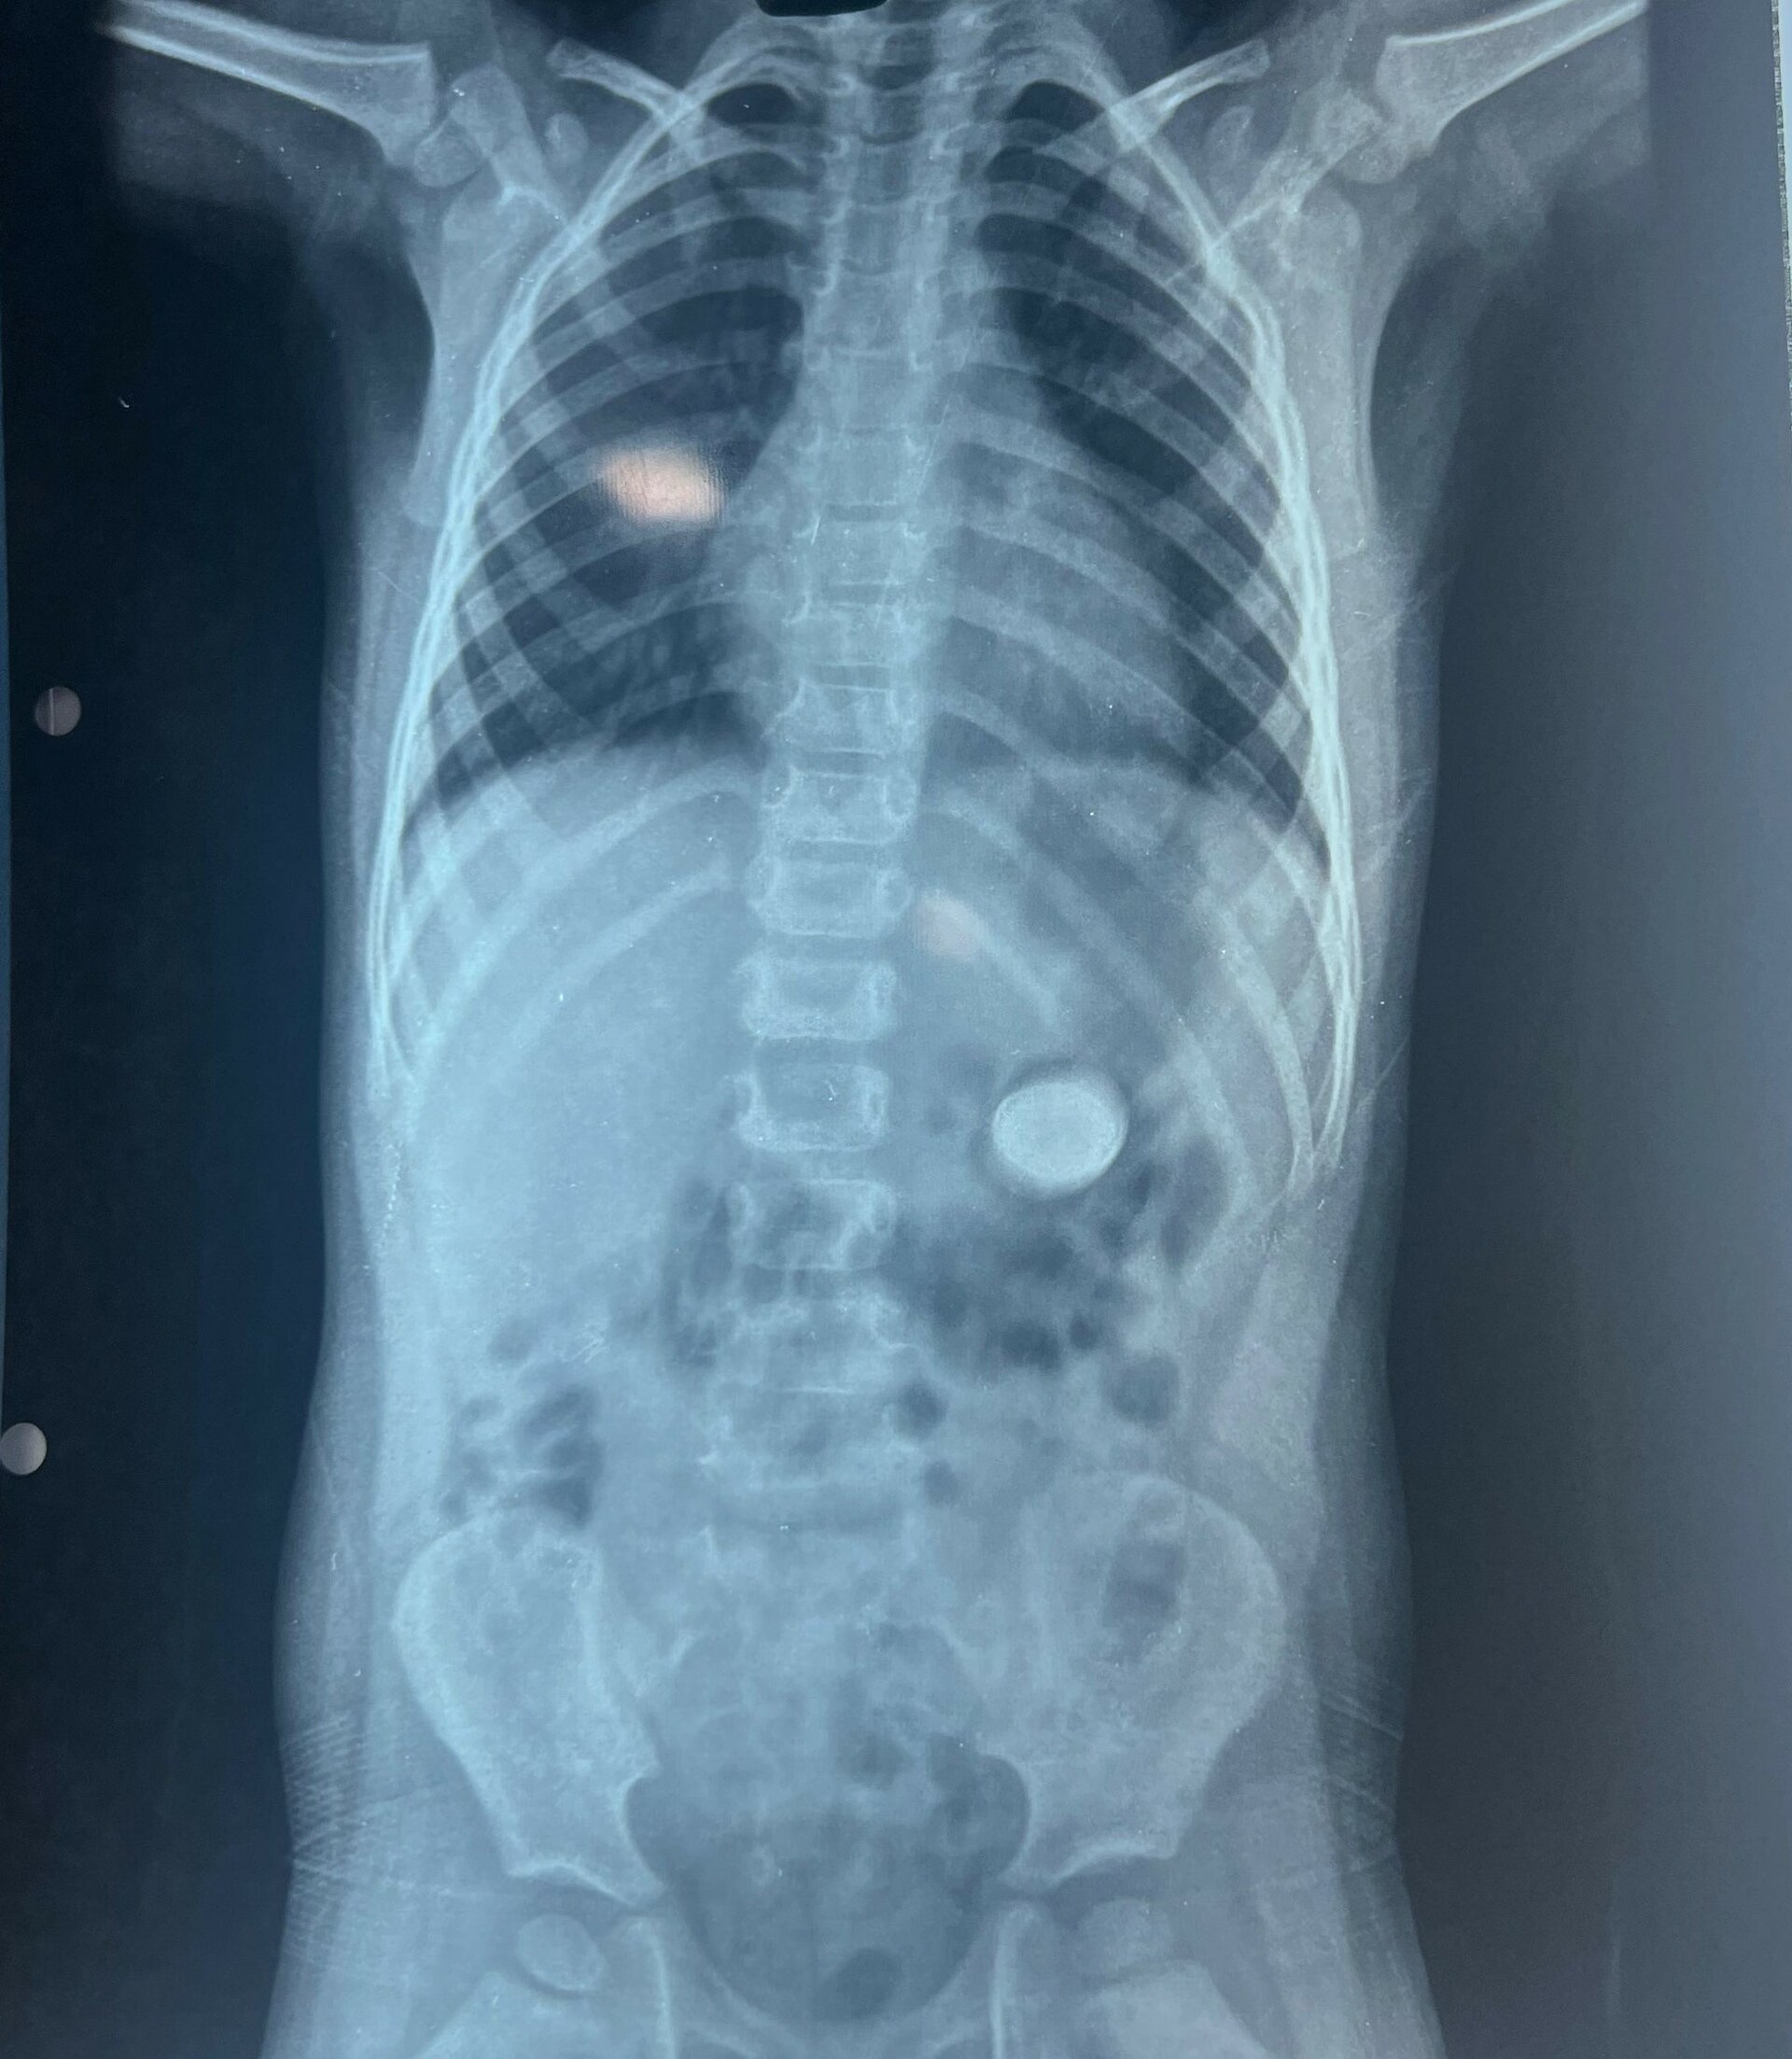

Pulse Hospital Successfully Completes 7th Pediatric Foreign Body Removal Case

In a remarkable feat, the team at Pulse Multi-Speciality Hospital successfully removed a lithium battery from the stomach of a 3-year-old child. Lithi...